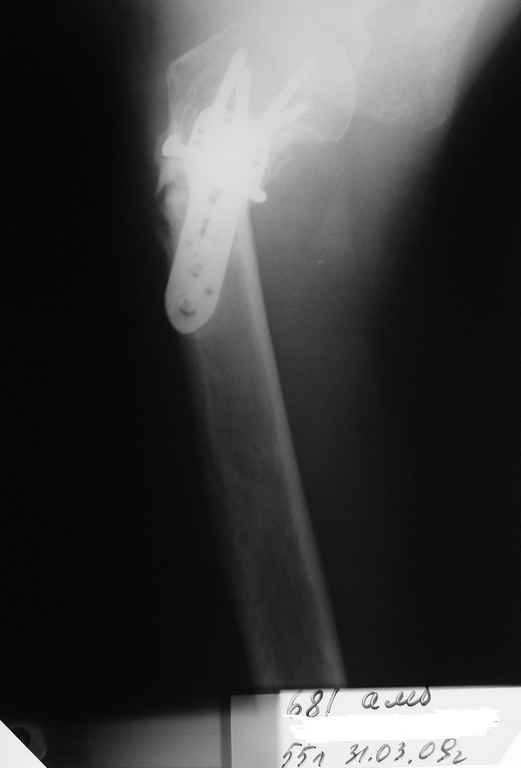

Пациентка Б.1953 г.р., врач-терапевт. Травма 27.11.08г. Падение с

высоты роста. Выявлен закрытый не осложненный оскольчатый перелом

хирургической шейки левого плеча со смещением.

02.12.08г. оперирована. Выполнена открытая репозиция и остеосинтез

пластиной LCP Деост с дополнительной фиксацией отдельно лежащего

фрагмента винтом. Послеоперационный период протекал без особенностей,

внутренняя ротация по 20 гр. На контрольных рентгенограммах

отмечается смещение металлоконструкции, ротация головки плеча с

приведением дистального отломка на 13 гр. и смещением к зади на 30 гр.

Рентгенограммы прилагаются. Ваш взгляд на дальнейшую тактику лечения

пациентки?